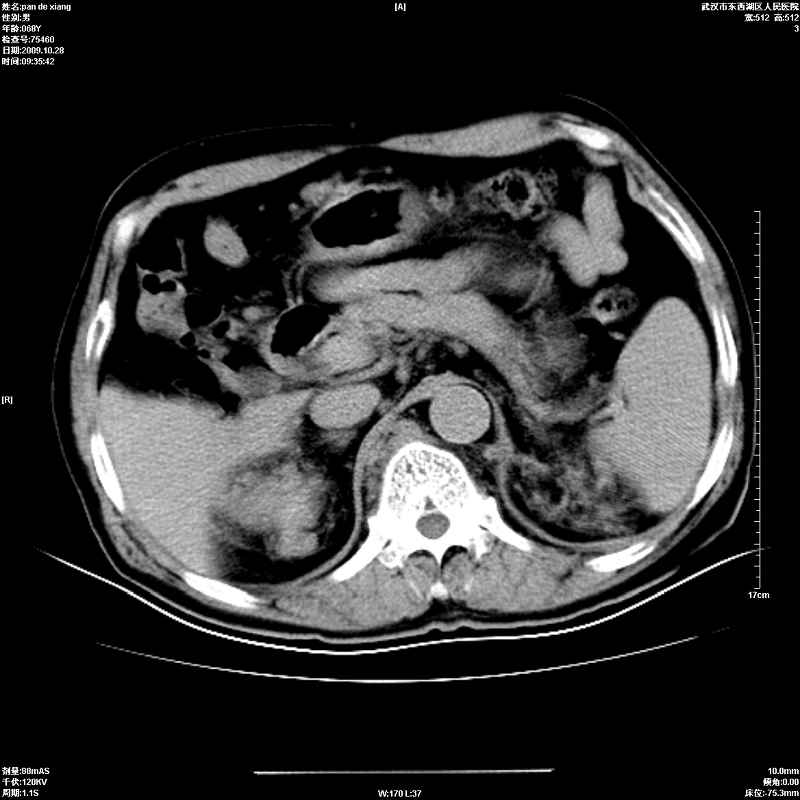

以下是引用杀毒软件在2009-10-28 20:41:00的发言:[br]结合临床考虑---白血病双肾改变或淋巴瘤。

以下是引用zxl51642在2009-10-29 9:59:00的发言:[br]结合临床“单克隆免疫球蛋白血症”,考虑双肾为继发损害并肾功能不全(尿中大量igg及少量iga、igm等大分子免疫球蛋白滤出所致继发损害),椎前软组织肿块为髓外造血。与浆细胞瘤有区别,平扫时有战友说的很清楚。